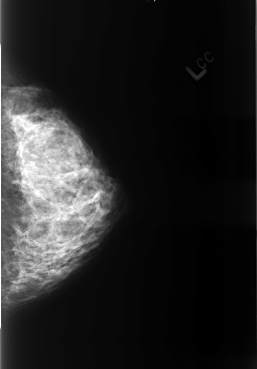

Volume: benign_without_callback_01 Case: B-3238-1

B_3238_1.LEFT_CC

PATIENT_AGE 47

DENSITY 4

LEFT_CC LINES 4424 PIXELS_PER_LINE 3080 BITS_PER_PIXEL 12 RESOLUTION 50 NON_OVERLAY